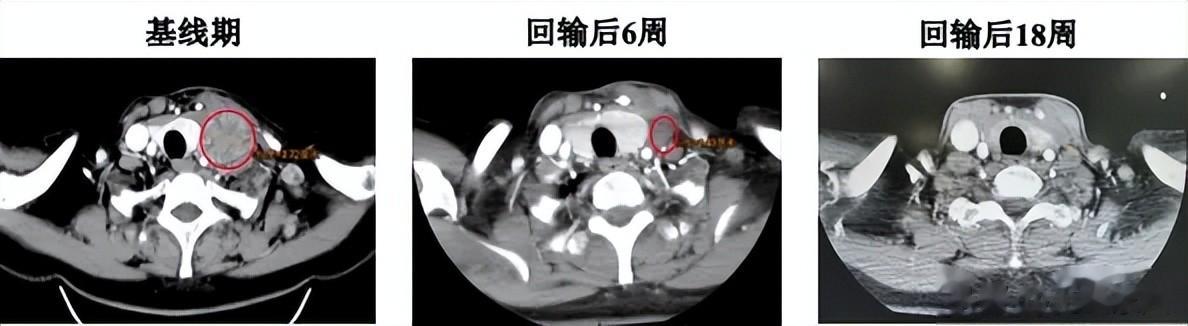

除此之外,还有一则令人鼓舞疗效的好消息!一例KRAS突变阳性肺癌受试者经GC101 TIL治疗18周后,疗效评估靶病灶达到完全缓解(CR),非靶病灶正逐渐消退,为KRAS突变阳性肺癌患者带来希望。

这是一例KRAS G12D突变的肺腺癌ⅣB期患者,自2022年4月出现左胸疼痛,确诊后先后接受免疫与化疗的联合治疗,以及免疫、抗血管生成抑制剂与化疗的联合治疗,都因疾病进展或不耐受停药。在现有治疗手段无效时,患者参加了君赛生物GC101 TIL细胞注射液注册临床试验。

TIL治疗过程,受试者除预处理过程短暂血液学毒性外无其他不良反应。回输第6周肿瘤缩小45%,肿瘤标志物恢复正常,癌痛减轻、颈部淋巴结消失;第12周靶病灶完全缓解(CR),18周时CR仍维持。

患者接受TIL治疗前和治疗后6周、18周增强CT扫描结果(左侧颈部淋巴结)

(图源上海九院官网,侵删)